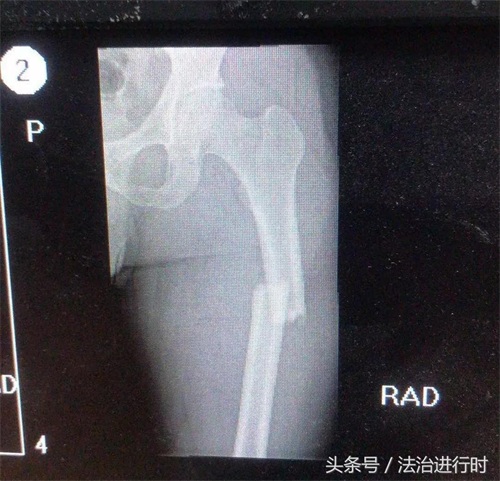

北京昌平90后刑警为追捕盗窃嫌犯大腿骨折

26日凌晨,北京市昌平公安分局刑侦支队民警王泽奇跳入大坑追捕一名嫌疑人致大腿骨折。说起当时的情形,他说:“当时就想着不能让那小子从我眼前跑了。”(中国长安网)